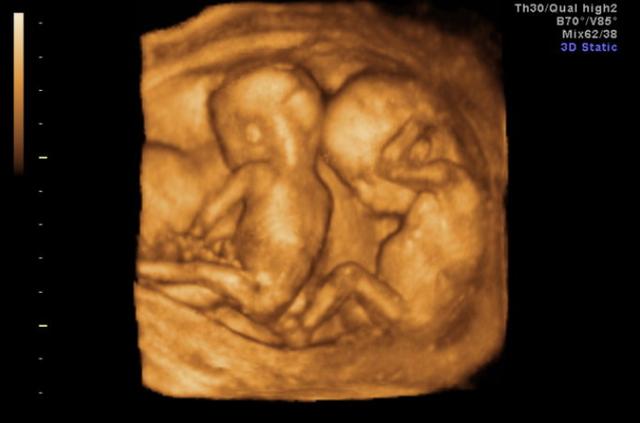

eft;” data-track=”22″>▼ 可能是怀了多胎没检查出来

一些孕妇怀孕后去医院检查,医院的设备可能没有检查出,孕妇肚子里的胎儿是双胞胎或多胞胎的情况,家里人也不知道,多胎的肚子自然比单胎更加显怀,显着肚子更大。